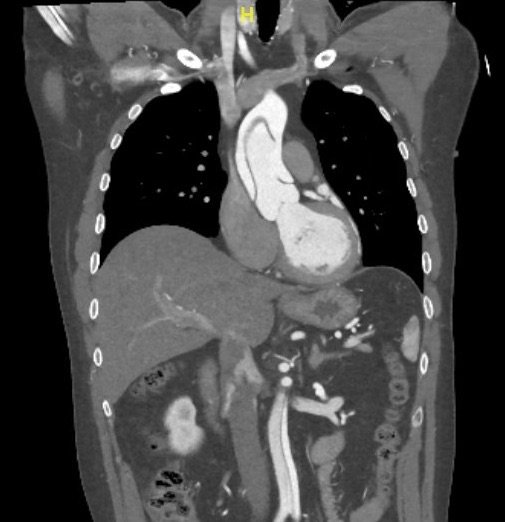

We present a case of a 51-year-old previously healthy man who presented to the ED complaining of chest pain that had resolved prior to arrival, and a mild headache. His vital signs were notable for hypotension, but physical exam was unremarkable. Chest x-ray revealed a borderline widened mediastinum. A standard ETTE was within normal limits, but additional SSNV demonstrated a dissection flap in the aortic arch. The patient was taken to the operating room for surgical repair 75 minutes after the ED ultrasound was performed; the operation was successful, and the patient was discharged to home post-operatively with good outcome.

Standard ETTE has limited ability to visualize the ascending aorta and aortic arch. Addition of SSNV allows visualization of these structures and may improve diagnostic accuracy and time to diagnosis of proximal aortic dissection.